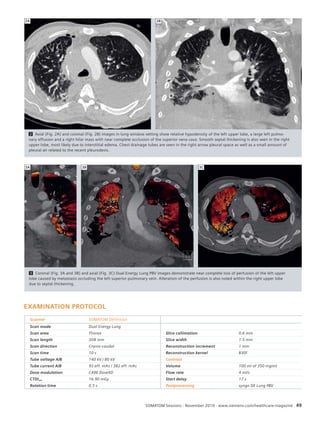

Dr. Pavel Ryska

News

Full Cardiac Assessment with syngo.via –

Maximal Signifi cance, Minimal Dose

Siemens has once again succeeded in taking another step forward in the fi eld

of CT diagnostics. By combining SOMATOM Scanners with the new syngo.via**